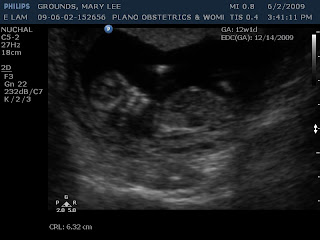

We will should hear back the results of the NT screening soon. Here are sonogram pictures until then! We did get a video of the sonogram and I will try to upload it if I can. Today's heart beat was 166 bpm. She tried to tell if it was a boy or girl, however, everything still looked like a mass of tissue. She said if the tissue was pointing straight up like a birthday hat or 12 o'clock then it's a boy; if it is pointing to 3 o'clock, then it's a girl. It was pointing to 1 o'clock...therefore, it will be my 18 week sonogram that will tell us if it is a boy or girl! Thank you to everyone who has kept us in their prayers.